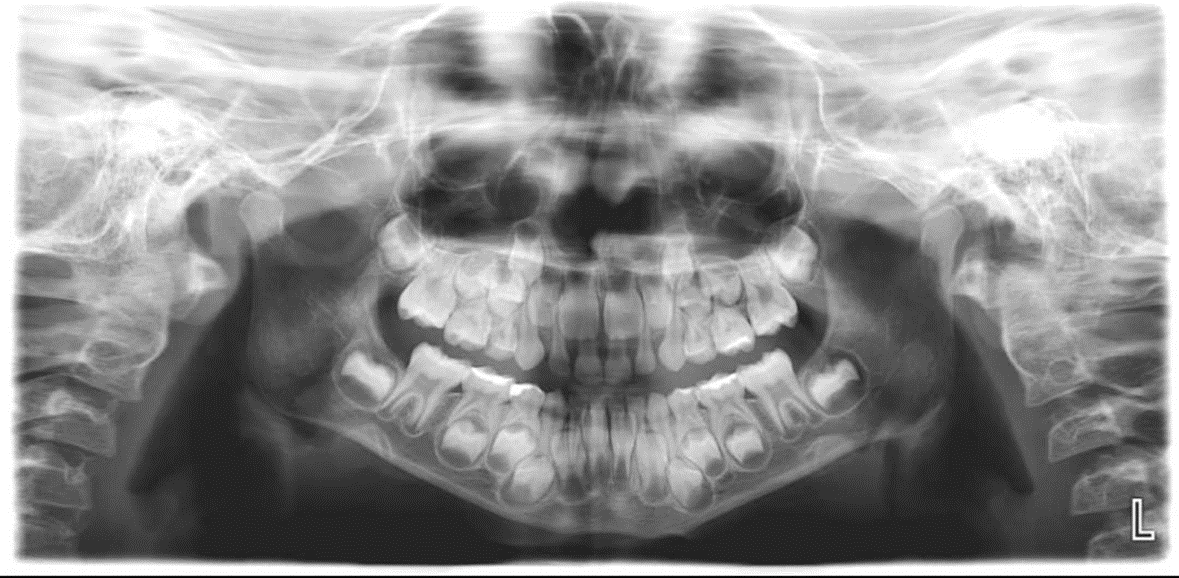

3. How old is the patient with the following X ray?